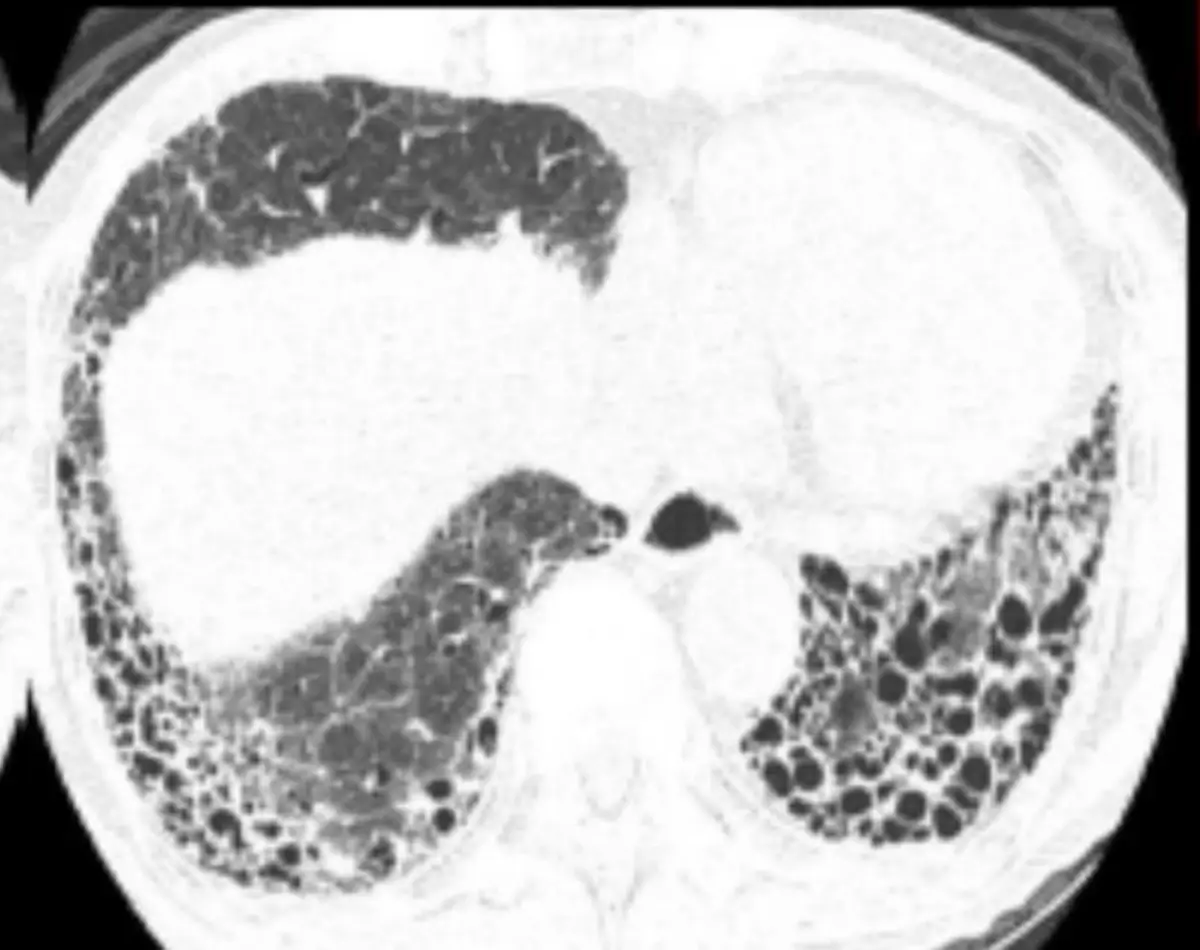

某90歲病人因乾咳與呼吸困難就醫,過去未曾吸菸。聽診時下肺葉有 crackles,胸部電腦斷層如圖所 示。下列肺功能與動脈血氣體分析結果何者最符合其診斷? 圖片描述

本題核心在於辨識 idiopathic pulmonary fibrosis(IPF)所呈現的 high-resolution CT(HRCT)影像特徵(subpleural、基底葉分布的網狀纖維化與蜂窩肺)以及相對應的肺功能檢查(PFT)與動脈血氣(ABG)表現:限制性通氣模式(↓FVC、↓FEV₁、正常或↑FEV₁/FVC)伴隨顯著↓DLCO,及其典型的輕度低氧血症、正常 PaCO₂。

從提供之胸部 HRCT,雙側下肺葉呈現:

• 皮質下(subpleural)與基底部(basal)對稱性網狀陰影,伴隨明顯的蜂窩肺特徵──多發大小相近、壁較厚的囊狀氣腔聚集,大小約 3–10 mm,可見囊腔層狀分布。

• 蜂窩肺常合併牽引性支氣管擴張,但此圖重點為典型蜂窩構造,符合 UIP(usual interstitial pneumonia)圖型,最常見於 IPF(ajronline.org)、(pubmed.ncbi.nlm.nih.gov)。